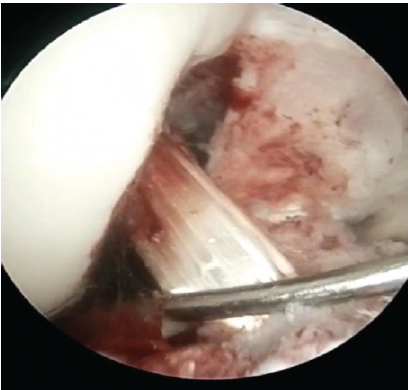

Flexor Carpi Radialis Tendon Stabilization for Chronic First Carpometacarpal Joint Instability: Clinical Outcomes from a Case Report

Akshay Punekar , Santosh D Ghoti , Mohammed Amjad Sohiel , Niranjan Sunil Ghag , Alok Yadav , Aditya A Agarwal